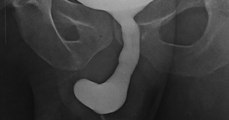

Operiert wegen Bauchschmerzen: Ärzte finden ungewöhnlichen Gegenstand im Rektum eines Patienten